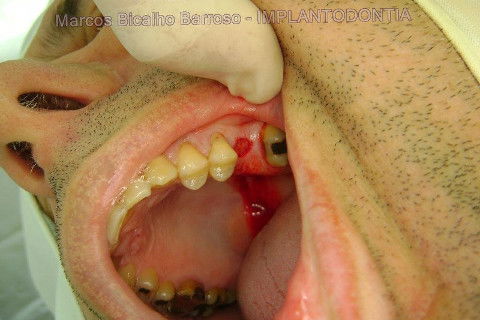

Instalação de um implante em região do 26. Utilizamos um implante cone morse Alvim Neodent 4.3 X 11,5. Foi uma cirurgia muito rápída e minimamente traumática, sem retalho e sutura.

Fotos do caso